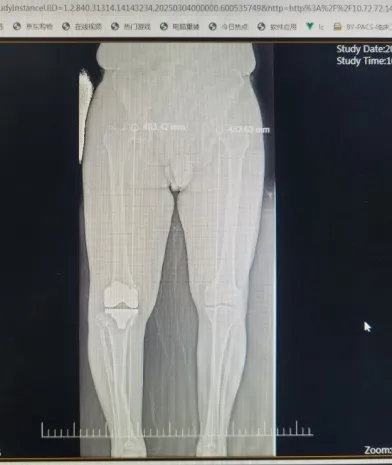

今年68岁的何爷爷是一位典型的右膝重度骨关节病患者。他右膝内翻畸形严重,行走时存在明显的跛行现象及O型腿,膝关节屈伸角度受限,下蹲困难,内侧胫骨平台缺损多,下肢力线极差,手术难度极大。多年来他饱受右膝疼痛的折磨,尤其在上下楼梯或长时间站立时,疼痛感更是明显加剧。